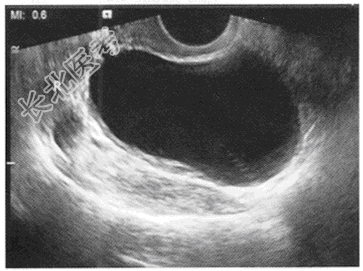

- 单项选择题女,25岁, B超检查如图所示,以下最可能的诊断为

A、右侧输卵管积液

B、扩张的右侧输尿管

C、右卵巢囊肿

D、右卵巢卵泡

E、右卵巢癌